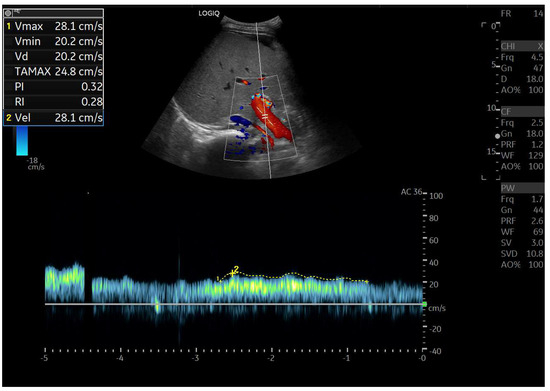

Abdominal ultrasound is a fundamental diagnostic tool in clinical practice, due to its availability, safety, and overall accuracy. This Special Issue will delve into the most recent technological and methodological innovations in abdominal ultrasound imaging, offering readers a comprehensive overview of advanced techniques, specific clinical indications, and solutions to emerging challenges. Among the various topics, it will cover the use of high-resolution probes, the integration of elastography for assessing liver fibrosis, and the application of contrast-enhanced ultrasound for identifying complex lesions. Strategies for training and professional development will also be examined to improve ultrasound performance and result interpretation.

- doppler